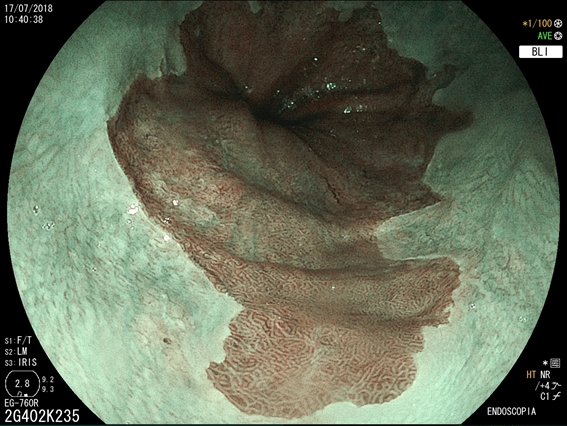

O que é Esôfago de Barrett?

Esôfago de Barrett é uma doença na qual há uma mudança anormal na mucosa do esôfago distal. A doença é causada principalmente pela exposição prolongada ao conteúdo ácido proveniente do estômago e está relacionado a um risco aumentado de câncer do esôfago. Esôfago de Barrett ocorre quando as células normais da porção inferior do esôfago são substituídas por um tipo diferente de células (semelhantes às do estômago). O Esôfago de Barrett normalmente é causado pelo refluxo gastroesofágico (RGE). Portanto, esta substituição das células do esôfago pelas células do estômago, muitas vezes é vista como um mecanismo de proteção ao ácido (as células do estômago são preparadas para resistir à acidez). É importante salientar que a maioria das pessoas que tem RGE nunca desenvolverão o Esôfago de Barrett, mas algumas podem desenvolver.Quais são os sintomas do Esôfago de Barrett?

Como detectar o Esôfago de Barrett?

O diagnóstico de Esôfago de Barrett é feito através da endoscopia digestiva alta com biópsia da área suspeita. O médico vai examinar com detalhes a região da transição entre o esôfago e o estômago e, se houver a suspeita de um epitélio anômalo na região, serão coletadas biópsias para análise no microscópio. A inspeção do Esôfago de Barrett deve ser realizada por endoscopista experiente e com aparelho de alta definição, para capturar detalhes suspeitos da mucosa.

Qual o risco do Esôfago de Barrett virar câncer?

Uma complicação do Esôfago de Barrett é que, com a agressão contínua do ácido no epitélio do esôfago, podem surgir células pré-malignas (displasias) que eventualmente podem crescer e virar um câncer invasivo. Estas lesões pré-malignas não costumam provocar sintomas, daí a importância de um acompanhamento médico. No entanto, a progressão do Barrett para um câncer é bastante incomum. Estudos que seguiram pacientes com Esôfago de Barrett, mostram que o risco de progressão para câncer é menor do que 0,5% ao ano.Como o Esôfago de Barrett é tratado?

Tratamento do Esôfago de Barrett com Radiofrequência

A ablação por radiofrequência usa calor para remover tecido pré-cancerígeno do esôfago de Barrett. A tecnologia do sistema de ablação por radiofrequência é projetada para a remoção de tecido afetado por Barrett, preservando o tecido saudável subjacente.Tratamento do Esôfago de Barrett com Mucosectomia

A mucosectomia é uma técnica empregada para ressecção do Esôfago de Barrett com lesões displásicas visíveis (pré-cancerígenas ou cancerígenas iniciais). Geralmente essa ressecção é realizada através da colocação de ligaduras elásticas, seguido da apreensão e corte com alça de polipectomia. O produto da ressecção é enviado para a análise histológica pelo patologista, a fim de verificar se o paciente está curado e para definir como será o acompanhamento no futuro.O que é gastrostomia endoscópica?